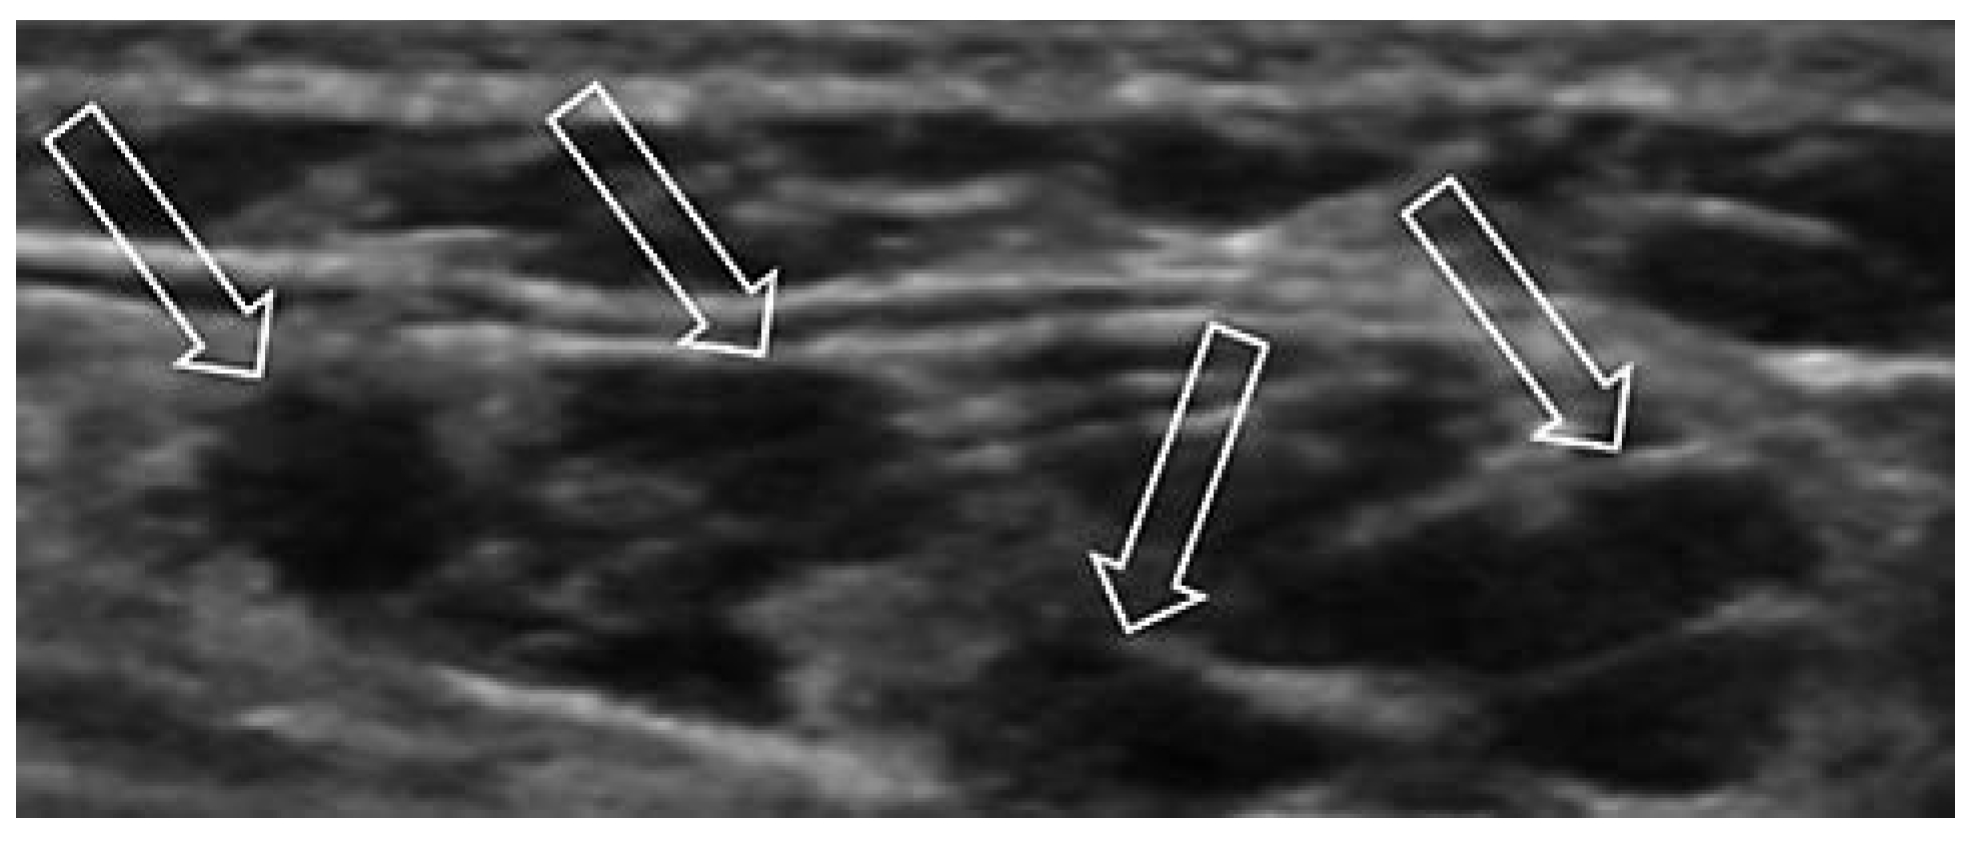

Venöse Malformationen